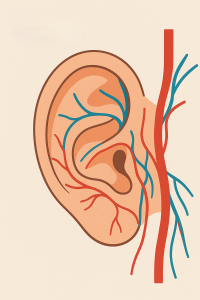

περισσοτεραΜικροσκοπική και Ενδοσκοπική Χειρουργική Ωτός

Τοποθέτηση και αφαίρεση σωληνίσκων αερισμού, πλαστική έξω ακουστικού πόρου…